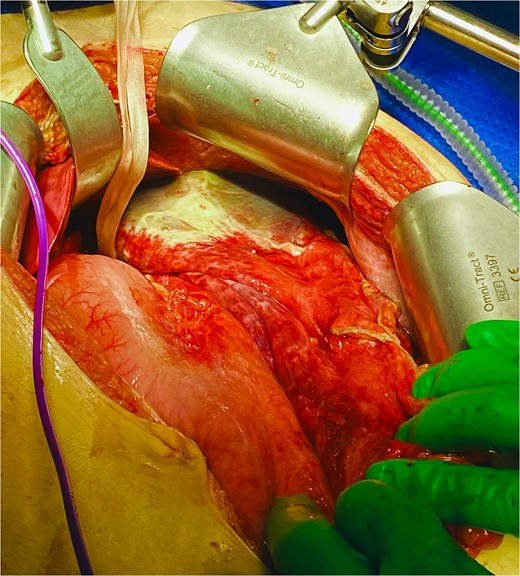

He was expedited to theatre, commencing with gastroscopy to exclude an intraluminal mechanical obstruction. There was widespread mucosal ulceration and necrosis (Figs 4–7) necessitating a laparotomy and assessment for transmural necrosis. The stomach was globally ischaemic with gangrene at the fundus (Figs 8–10) and hence a total gastrectomy was performed and reconstructed with roux-en-y oesophagojejunostomy and jejunojejunostomy.

Total gastrectomy specimen showing areas of gangrene and necrosis.

Histopathology confirmed widespread ischaemic changes marked oedema, blood, and extensive mucosal necrosis with multiple focal areas of full thickness necrosis.